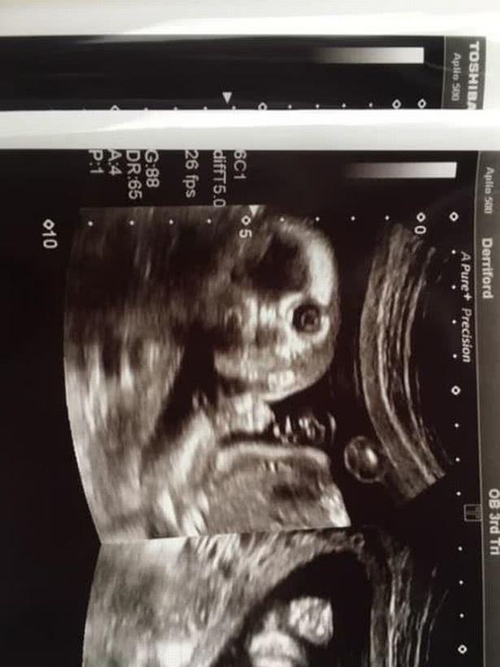

英国准妈妈怀孕20周,b超照片太好玩,胎儿直视镜头像小鬼

宝宝彩超图

怀孕20周胎儿图片

怀孕20周胎儿真实图片

怀孕20周胎儿高清图片